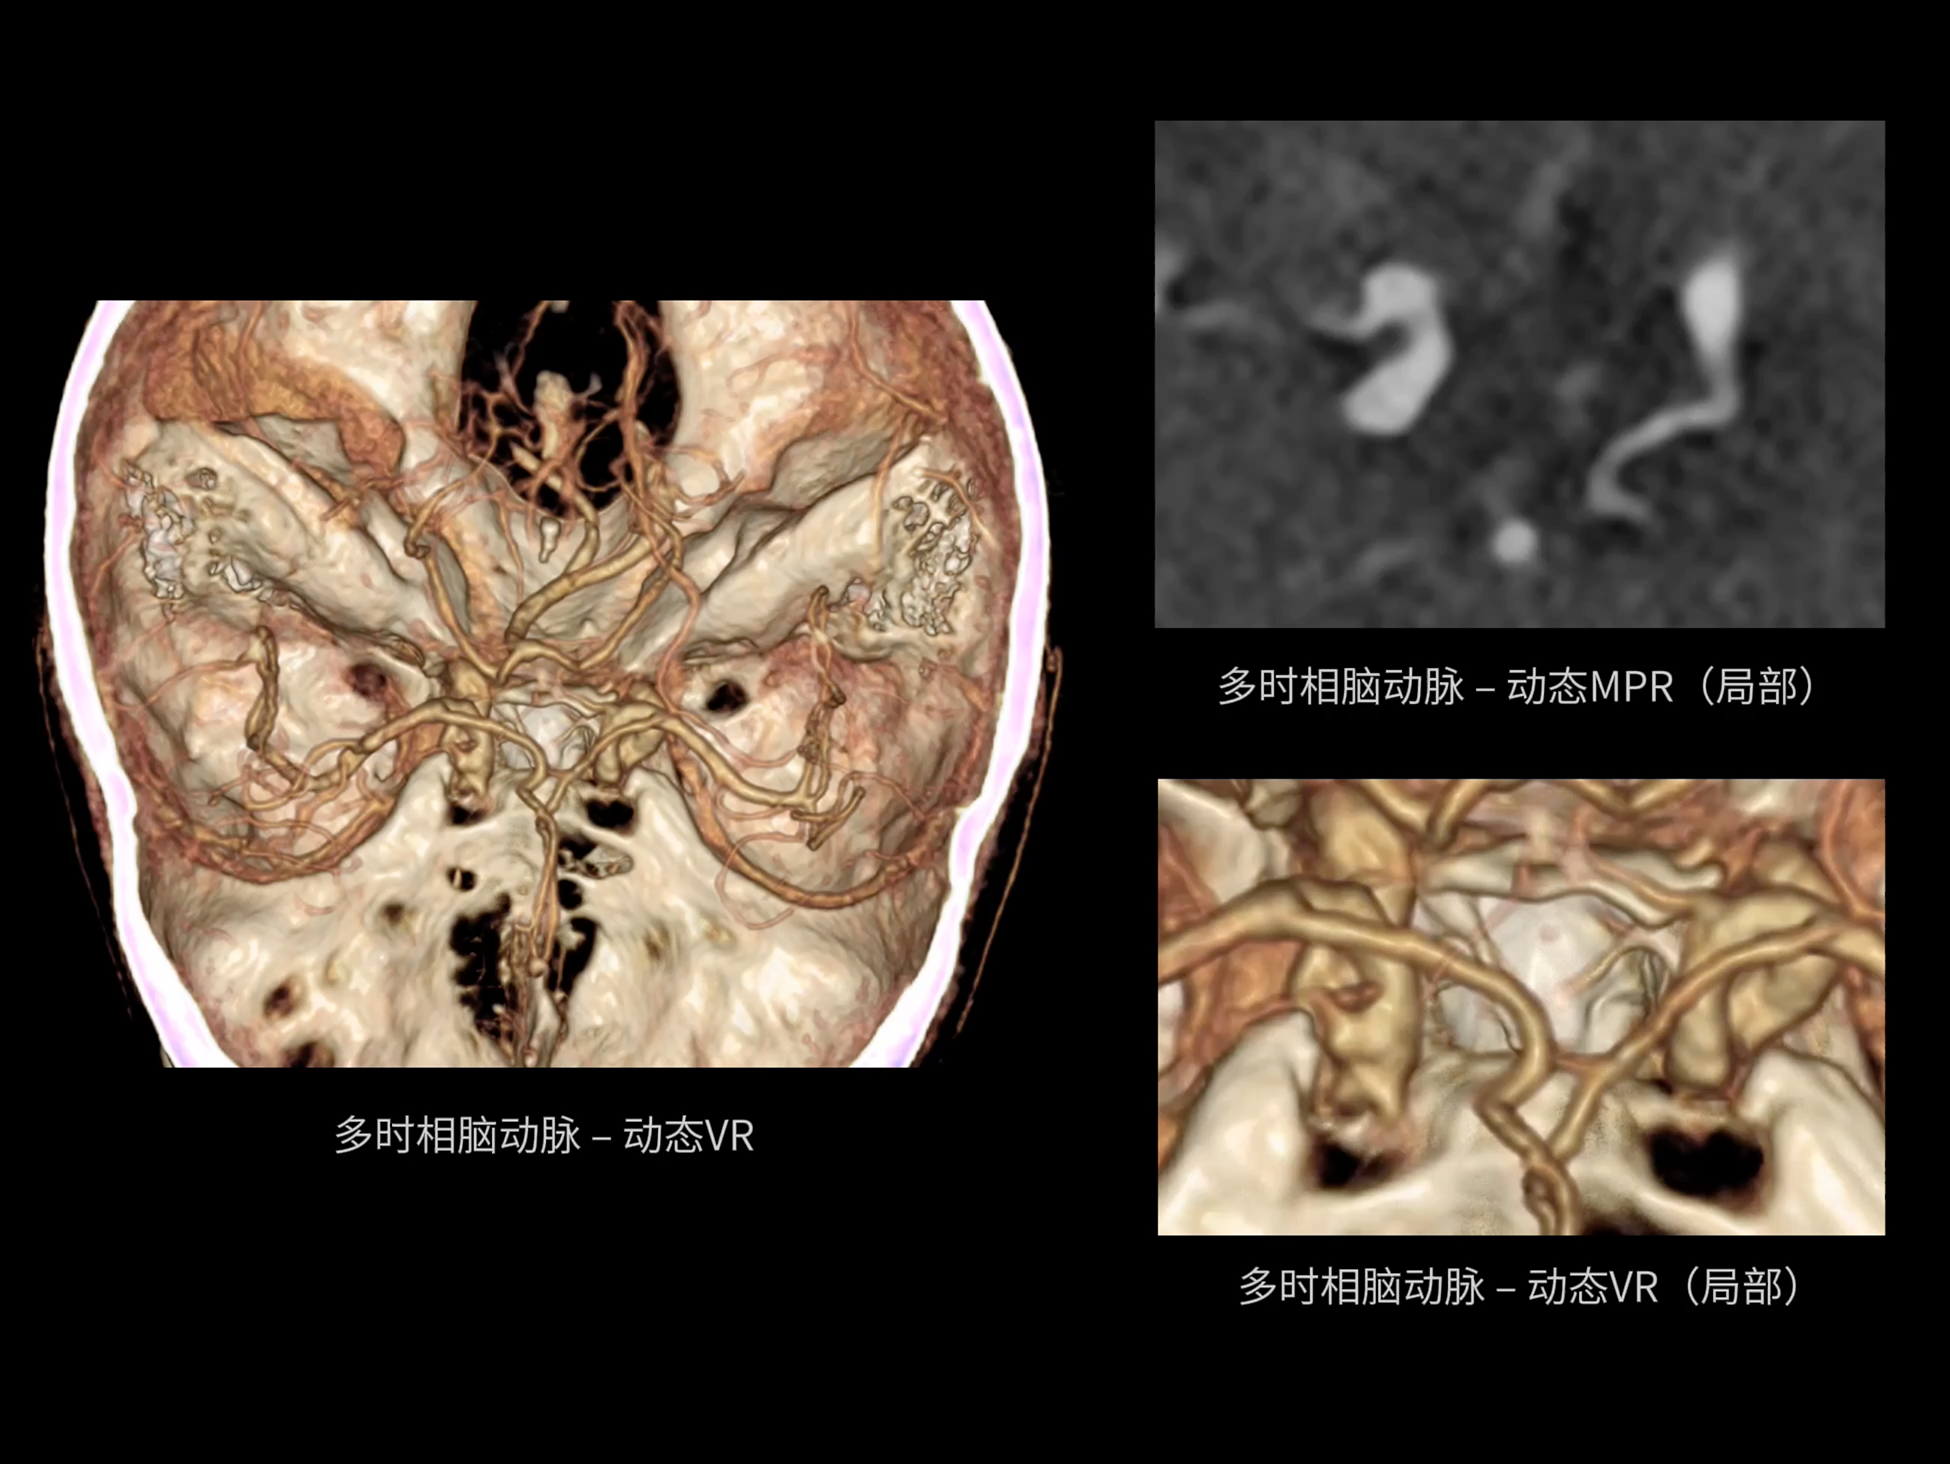

全域能谱

uCT SiriuX® 依托16cm超宽探测器与双源能谱技术,实现真正意义上的全身高清能谱成像。单次扫描同步获取灌注、能谱等多维定量参数,精准解析组织特性与病灶成分,为临床决策提供更深层次的诊断依据。

全身高清能谱成像

uCT SiriuX® 采用独有的双宽体探测器设计,实现470mm超大视野与全脏器容积覆盖的能谱成像,轻松应对不同体型患者和扫描部位应用需求。配合创新能谱重建影像链与精准双能数据配准,系统可有效抑制伪影、提升信噪比,在全脏器范围内提供高质量能谱图像,显著拓展临床精准诊断的广度与深度。

470 mm

• 双宽大视野

• 支持全身各部位能谱成像

SpeX

• 双能高精配准与硬化伪影校正

• 高清能谱分解&降噪重建技术

• 支持全身各部位、各类能谱成像

全面能谱分析工具

能谱成像可揭示丰富的物质与能量信息,其临床价值的充分释放有赖于完善高效的后处理分析平台。uCT SiriuX® 提供全面能谱高级分析工具,覆盖心血管、肿瘤、神经、骨科等多类临床场景。平台支持动脉增强分数分析(AEF)、细胞外容积分析(ECV)、肿瘤同源性分析、肺栓塞分析、骨髓水肿分析等多项评估,并提供多达10种基物质对成像,为精准诊断与科研探索提供坚实支撑。